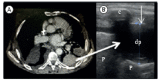

Lung ultrasound in the evaluation of pleural effusion